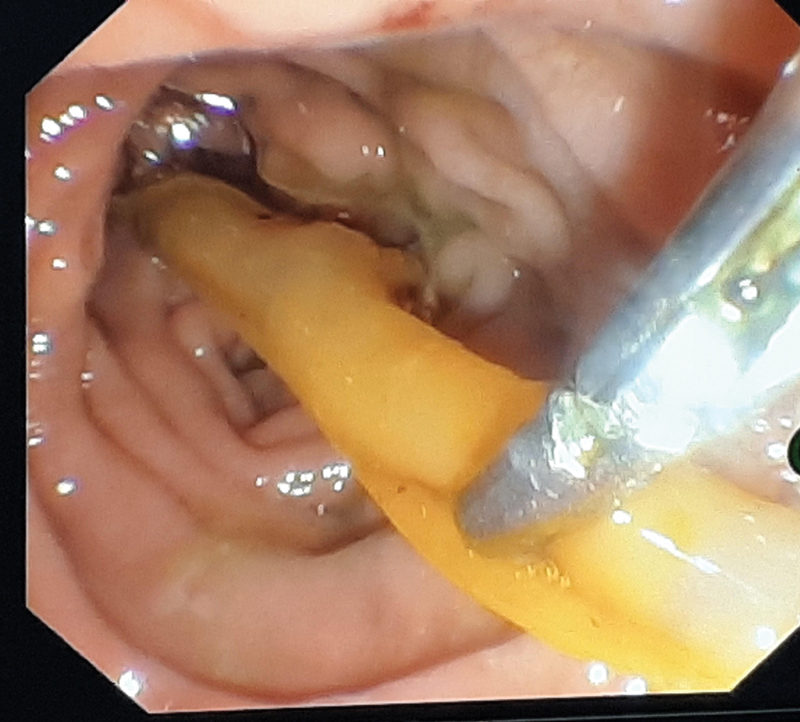

On follow-up at 3 weeks, the patient was doing well, and hence, T tube removal was planned. However, it got fractured at the junction between the short and long limbs on attempted removal, and only the long segment of the T tube could be retrieved. The patient was admitted and kept under close monitoring. A plain X-ray abdomen was done, which showed radiopaque linear intensity over the right paravertebral location suggestive of a retained T tube fragment. MRCP showed dilated CBD ∼9.3 mm with a T tube remnant approximately 2 cm length, in mid and distal CBDs ( Fig. 2 ). ERCP, done this time by a different endoscopist, showed a radiopaque structure in the mid and distal CBDs, retrieved by balloon catheter postsphincterotomy followed by the placement of a bile duct stent ( Fig. 3 ). T tube fragment was inspected for its entirety ( Fig. 4 ). No adverse events were reported at 2 weeks to follow, and the CBD stent was removed without any subsequent complications.